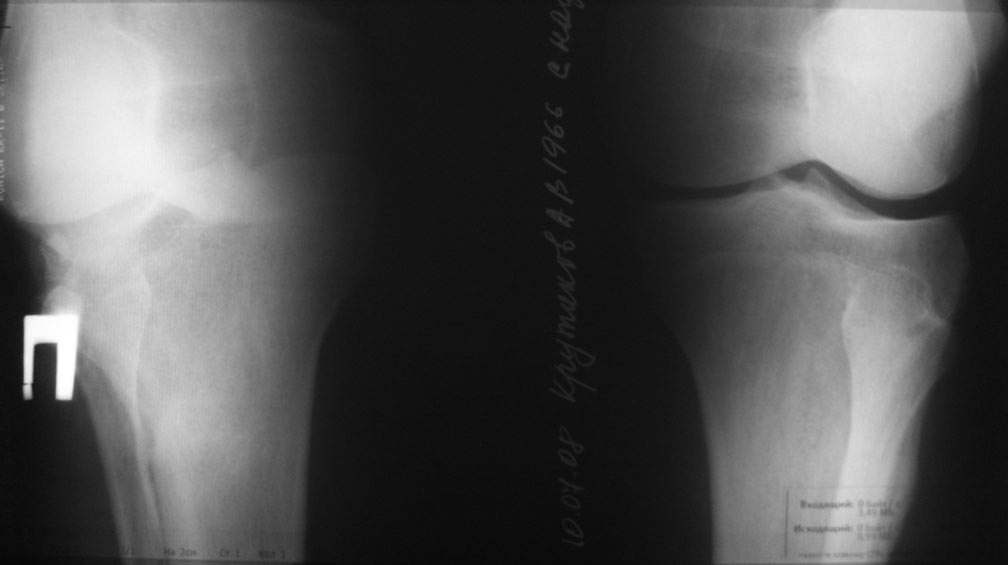

пациент наконец то объявился вновь и мы смогли выполнить новые снимки как лежа так и в нагрузке